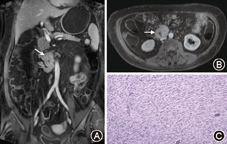

53例患者均完成MRE检查,其中诊断小肠克罗恩病12例(图1)、小肠息肉3例、小肠间质瘤3例(图2)、小肠憩室炎2例、慢性阑尾炎2例,溃疡性结肠炎3例,结肠癌1例,始基子宫1例,无器质性肠道疾病14例。12例小肠克罗恩病,MRE显示6例病变累及回盲部或末段回肠,6例表现为多节段小肠受累,受累部位肠病厚度>4 mm,强化信号比值>1.3,诊断灵敏度和特异度均为100%。缺血性肠病、小肠血管发育畸形和NASID表现为肠管的局部或阶段性管壁增厚和(或)明显强化,定位诊断正确,定性诊断为良性病灶,考虑局部肠壁炎症;2例小肠息肉于MRE未能显示(假阴性)。2例无器质性肠病患者局部肠管充盈不良,MRE考虑为局部炎症(假阳性)。ROC曲线显示MRE发现小肠病灶的曲线下面积0.900(95%CI 0.750~1.000)(P<0.01); MRE诊断小肠病灶的曲线下面积0.729(95%CI 0.573~0.884)(P<0.01); MRE和胶囊内镜两种方法在发现小肠病灶具有相关性(χ2=28.800,P=0.000),kappa值=0.800,这提示两种方法在发现小肠疾病中具有很好一致性。MRE和胶囊内镜两种方法诊断小肠疾病具有相关性(χ2=12.600,P=0.000),kappa值=0.462,这提示两种方法在诊断小肠疾病具有中度一致性。

MRE的一个重要诊断价值就是诊断克罗恩病[7]。本组研究中,以肠壁增厚>4 mm,强化信号比值>1.3为诊断标准。发现的12例克罗恩患者中,6例病变累及回盲部或末段回肠,为克罗恩病的典型患病部位;6例表现为多节段小肠受累,符合克罗恩病多发的特点;此外MRE发现2例克罗恩患者合并肠系膜淋巴结增大[8],显示MRE能够观察到克罗恩病肠外改变。研究表明[9],>15 mm的结节样病变MRE都可以检出,而<5~10 mm的病变检出率相对较低,对于<5 mm的病变是无法检出的。本研究中MRE对于肿瘤及息肉结节样病变的检出显示了较高的敏感性,通常需要在增强序列中观察。本组共8例结节样病变,其中3例为间质瘤,术前获得正确诊断;3例为多发息肉。多发息肉病变均在增强序列明确发现,而在平扫序列未能全部显示,病灶介于0.5~1.0 cm,多发。此外2例小肠息肉直径<1 cm,胶囊内镜检测到,MRE未见明显强化。